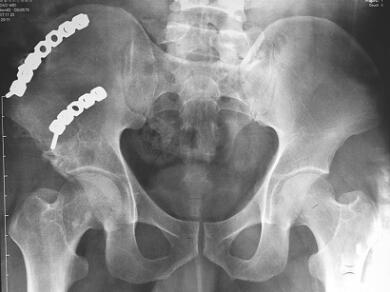

查体:骨盆部不对称,双侧髂前上棘对称,可见长约25cm手术切口痕,右下腹有一30cm类椭圆形膨隆包块,质软,推之可回纳,听诊有正常肠鸣音;无腹部压痛与反跳痛,透光试验阴性;无骨异常活动,骨盆挤压分离试验、4字试验阴性。拍摄X线片(图1)示:右侧髂骨骨折钢板固定术后,骨折线消失;耻骨联合间隙正常,双侧骶髂关节正常。腹部CT示右侧腹壁菲薄,腹肌大部分未附着髂嵴,腹内容物移位、突出于髂嵴外,但是腹膜与肠之间尚有间隙。入院诊断:右髂骨骨折术后继发腹壁疝。

图1腹壁疝修补前骨盆平片及CT片